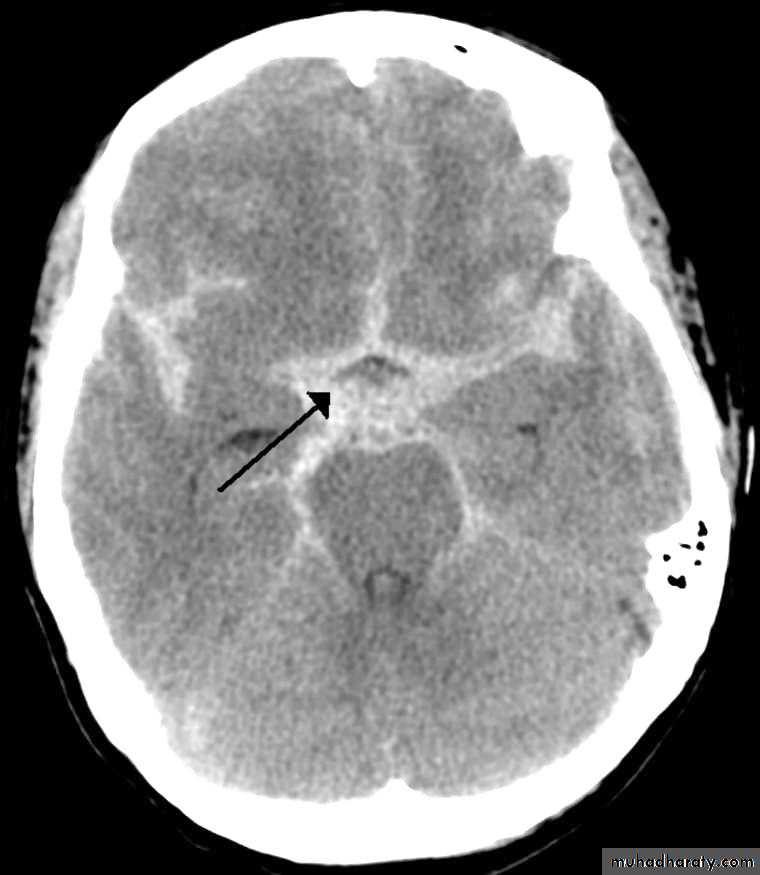

CT /MRI the best to detect heamoorage is brain CT

Computed tomography (CT) scan: will detect subarachnoid blood in more than 90% of patients

Spontaneous ICH results from intracerebral arterial rupture, particularly perforating vessels. The haematoma expands following the path of least resistance, usually along white matter tracts, and occasionally into the ventricular system.

ICH